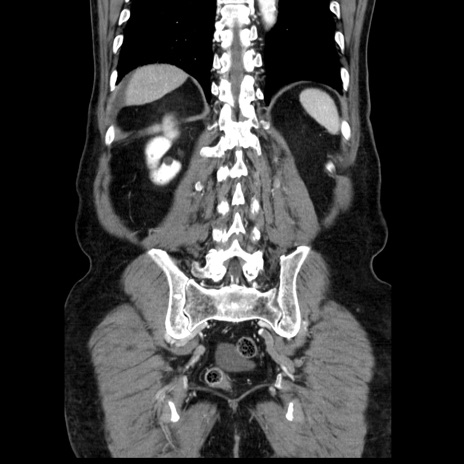

症例30(冠状断像)

【症例】80歳代男性

【主訴】臍周囲痛

【現病歴】約6時間前から臍下部痛が出現。次第に腹部膨隆・背部痛も生じてきたため来院。背部痛の場所は変化しない。

【身体所見】意識清明、BT 36.3℃、BP  131/87mmHg、P 87bpm、SpO2 100%(RA)、臍周囲自発痛・圧痛あり、反跳痛なし、自発痛部位に一致して板状硬あり、腹部膨隆、腸雑音減弱、CVA tenderness両側陰性。